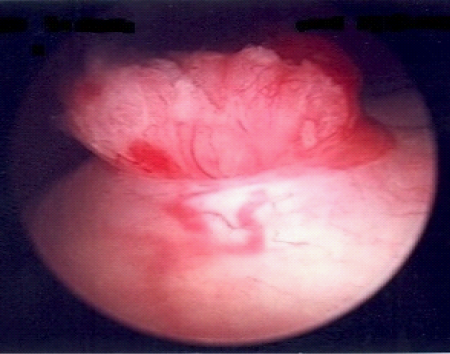

MRI revealed a large pelvic mass extending from the cervix that was associated with severe right hydroureter, anterior displacement of the bladder, and bladder invasion at the level of the trigone (Figure 1). On cystoscopy, the bladder base, lateral walls, anterior wall and dome were free of lesions; however gross intraluminal tumor was protruding from the right ureteral orifice (Figure 2). A biopsy of the tumor was taken and the patient underwent right PCN placement. Pathologic analysis from the biopsy revealed adenocarcinoma consistent with an endocervical origin. Based on the pathologic findings, the patient’s disease was classified as stage IVA and she was started on platinum-based chemotherapy and pelvic radiation.

Figure 1 Magnetic resonance imaging (MRI) with contrast revealing severe right hydroureter (arrow).